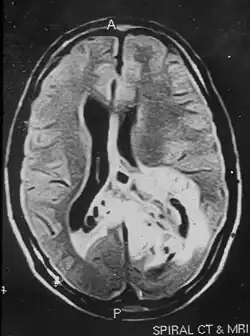

Due to the large range of causes that lead to micropsia, diagnosis varies among cases. Computed tomography (CT) and magnetic resonance imaging (MRI) may find lesions and hypodense areas in the temporal and occipital lobes.[4] MRI and CT techniques are able to rule out lesions as the cause for micropsia, but are not sufficient to diagnose the most common causes.